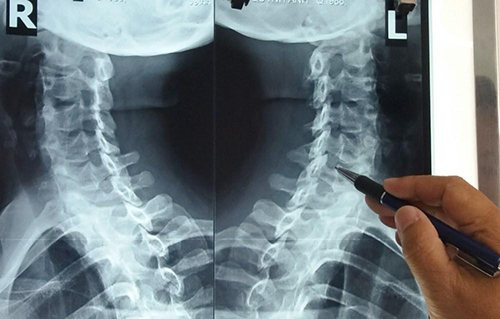

Các chuyên gia Sức khỏe và đời sống của Bộ Y Tế cho biết, thoái hóa khớp là tình trạng hư hỏng phần sụn, đệm giữa hai đầu xương có kèm theo phản ứng viêm và giảm sút lượng dịch nhày giúp bôi trơn, do đó gây đau và cứng khớp. Bệnh chủ yêu gặp ở người trên 40 tuổi đặc biệt là sau 60 tuổi.Có hai loại bệnh thoái hóa khớp điển hình sau:- Thoái hóa khớp tiên phát: ví dụ khớp háng, khớp đầu gối, khớp bàn ngón chân cái, khớp bàn ngón và khớp ngón gần của ngón tay cái, cột sống cổ, cột sống thắt lưng...- Thoái hóa thứ phát: là hậu quả của tổn thương khớp do những nguyên nhân tại khớp (như viêm khớp dạng thấp), hay ngoài khớp. Thoái hóa thứ phát có thể xuất hiện ở bất kỳ khớp nào.